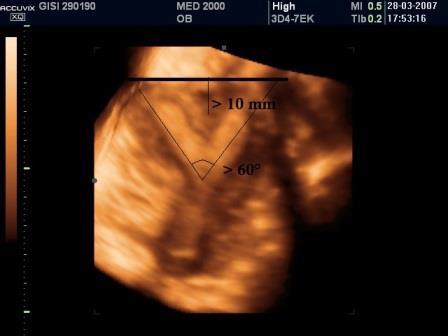

Utero Bicorne

L'utero bicorne è conseguenza della mancata o incompleta fusione dei dotti di Muller e rappresenta circa il 10% di tutte le anomalie mulleriane. E' caratterizzato dalla presenza di due distinti corni uterini divergenti che si fondono verso il fondo dell'utero o a livello del segmento uterino inferiore o a livello dell'istmo ( utero bicorne unicolle).

Dal punto di vista ecografico si osserva una divergenza degli echi endometriali, meglio evidente alla elaborazione 3D. Importante la diagnosi differenziale con l'utero setto (nell'utero bicorne si ha una incisura del fondo uterino maggiore di 10 mm.) e con l'utero didelfo (nell'utero bicorne i due corpi sono separati tra di loro da un angolo superiore a 60°).

Se si associa la presenza di una vagina atresica o di setti vaginali (25% dei casi) possono associarsi anomalie dell'apparato urinario (agenesia renale, rene ipotrofico, ectopia renale).

L'utero bicorne non è causa di infertilità ma sono più frequenti gli aborti spontanei nel I trimestre e soprattutto il parto pretermine, perchè le due cavità uterine sono più piccole.

E' importante sottolineare che anche l'utero bicorne non è incompatibile con il completamento di una gravidanza fisiologica.